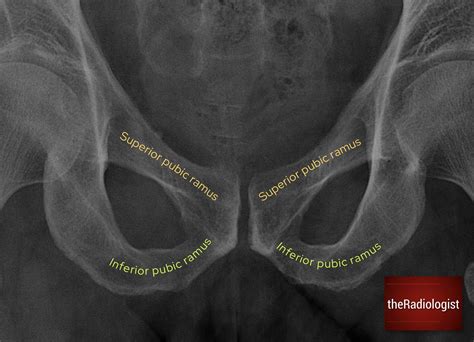

To truly grasp the significance of the inferior pubic ramus, one must understand its position within the pelvic girdle. The pelvis is composed of three primary bones that fuse together during maturation: the ilium, the ischium, and the pubis. The pubis itself is divided into a body and two branches, known as rami. The inferior pubic ramus is the thin, flattened branch that extends downward, backward, and laterally from the body of the pubis to join the ischial ramus.

This anatomical junction is essential for forming the obturator foramen, a large opening in the pelvic bone that allows for the passage of nerves and blood vessels to the lower limbs. Because of its location and structure, this part of the bone is a common site for stress and injury, particularly in high-impact activities or traumatic accidents.